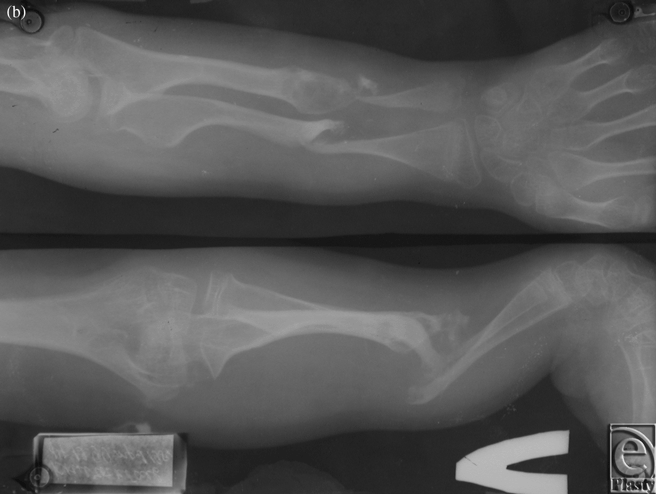

Case 1: Congenital pseudarthrosis forearm

The patient was an 8-year-old boy who suffered from congenital pseudarthrosis forearm type II on both the radius and the ulna. After resection and Ilizarov external fixation/traction, the discrepant 8-cm-long space between the 2 sides was repaired. A secondary free fibula osteoseptocutaneous flap was then harvested from the contralateral side and transferred to the affected side to cover the tissue defects (Figs 1a-1e).

| Figure 1. Case 1: Congenital pseudarthrosis forearm. (a) Preoperative view, (b) Preoperative x-ray, (c) External fixation, (d) The 1-year postoperative view, and (e) A 1-year postoperative x-ray. |